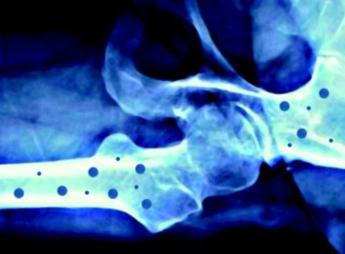

L’iniziativa ha il supporto incondizionato di Ibsa Farmaceutici Italia come main sponsor, e di Gedeon Richter, Organon, Accord Healthcare Italia, Ucb e Theramex come silver sponsor. Sono le aziende farmaceutiche che hanno scelto di sostenerne questi importanti progetti di informazione che, grazie a loro, possono essere portati avanti. L’osteoporosi – conclude la nota – è una malattia sistemica dell'apparato scheletrico, caratterizzata da una bassa densità minerale e dal deterioramento della micro-architettura del tessuto osseo, con conseguente aumento della fragilità ossea e del rischio di fratturarsi. —salutewebinfo@adnkronos.com (Web Info)